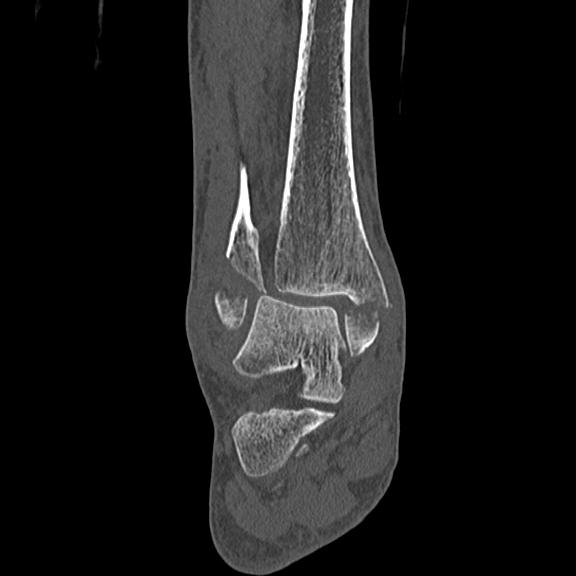

102755 1/4 2R 1/15 2R 右足関節 68歳女性 右三果脱臼骨折